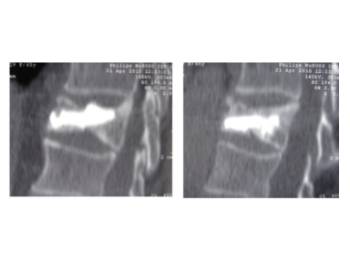

Pre- and post-operative comparison of a cemented kyphoplasty

Female, age 55, compression fracture of L2

Before 1

After 1